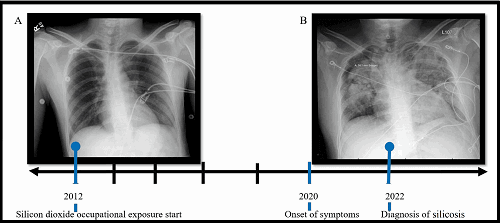

Chest x-ray transition showing accelerated silicosis, with image (A) showing the chest X-ray 10 years prior and (B) the chest X-ray at the time of diagnosis. Photograph: From an article by Patino S, Izquierdo-Pretel G (July 05, 2022) A Case Report of Accelerated Pulmonary Silicosis